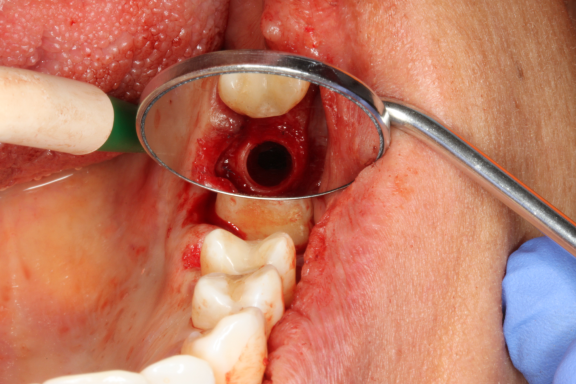

Die Implantat Entfernung in unserer Praxis

Bei der Implantat- Entfernung wird sehr genau gearbeitet, sodass keine Titanpartikel durch die Ausbohrung im Knochen zurückbleiben. Die Entfernung von Titanimplantaten erfordert nicht nur eine fachmännische chirurgische Technik, sondern auch eine umfassende Nachsorge (z.B. Schwermetallausleitung), um eine schnelle Genesung zu gewährleisten.

Unsere Praxis ist mit neuen Technologien und Materialien ausgestattet, um diesen Prozess so schonend wie möglich zu gestalten. In der Regel ist es möglich, die Titanimplantate aus dem Knochen herauszudrehen, ohne einen Knochendefekt zu hinterlassen.

Nach der Entfernung der Titanimplantate können bei gesundem Knochen Keramikimplantate sofort gesetzt werden. Mit dem unmittelbaren Austausch von Titan zu Keramik wird Zeit gewonnen, so kann das neue Implantat in dieselbe Stelle eingearbeitet und Knochenverlust vermieden werden.